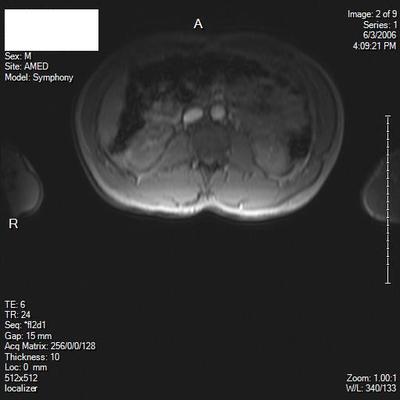

I'm 35 years old, male. Right hip pain, started as low back pain. Herniated disc L5S1, treated with ESI injections. Still have hip pain. Hurts when I flex my leg, SLR pain at about 45 degrees. My MRI and Xray are only of lumbar spine, however, do you see any abnormality of any bony or soft tissue of hip on these images? I understand it could be sciatica, which was the easiest thing they could come up with.

Two of the scan views are poor and I'm unable to determine what level; there's a suggestion of the fat squeezed out of the IVF on the right, but I wouldn't much store from that.

From what's visible of the hips they appear normal to me.

I'm trying to locate any other pathology. Is their any muscle atrophy? Or other bursitis, soft tissue, tendon?

There's normally fat in the IVF; if it's been squeezed out there's likelihood of a disc prolapse into the foramen.